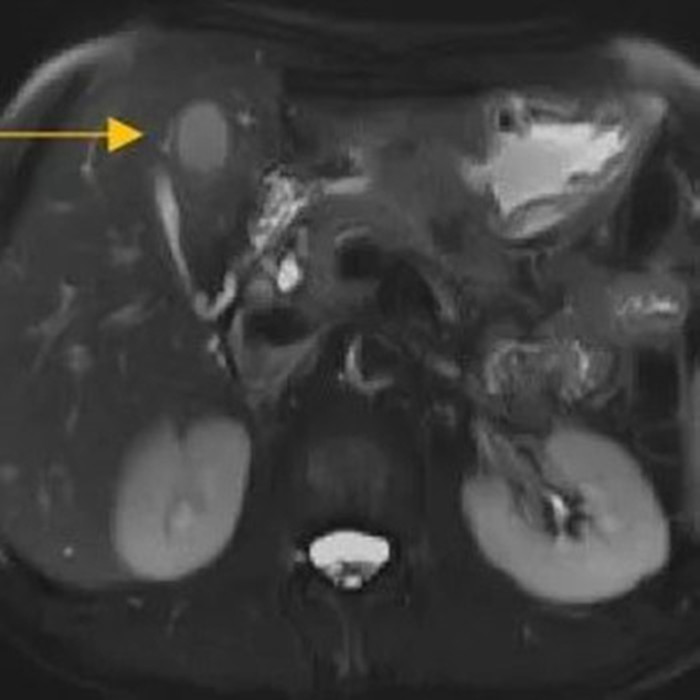

經(jīng)過6個周期,前后4個月的治療,周先生再次復(fù)查CT,提示胃部腫瘤,轉(zhuǎn)移的胃旁淋巴結(jié)、肝臟腫瘤都有明顯縮小,營養(yǎng)狀況良好,能正常進(jìn)食,體重增加了6斤,精神狀態(tài)比原先好了很多。

治療前

治療后